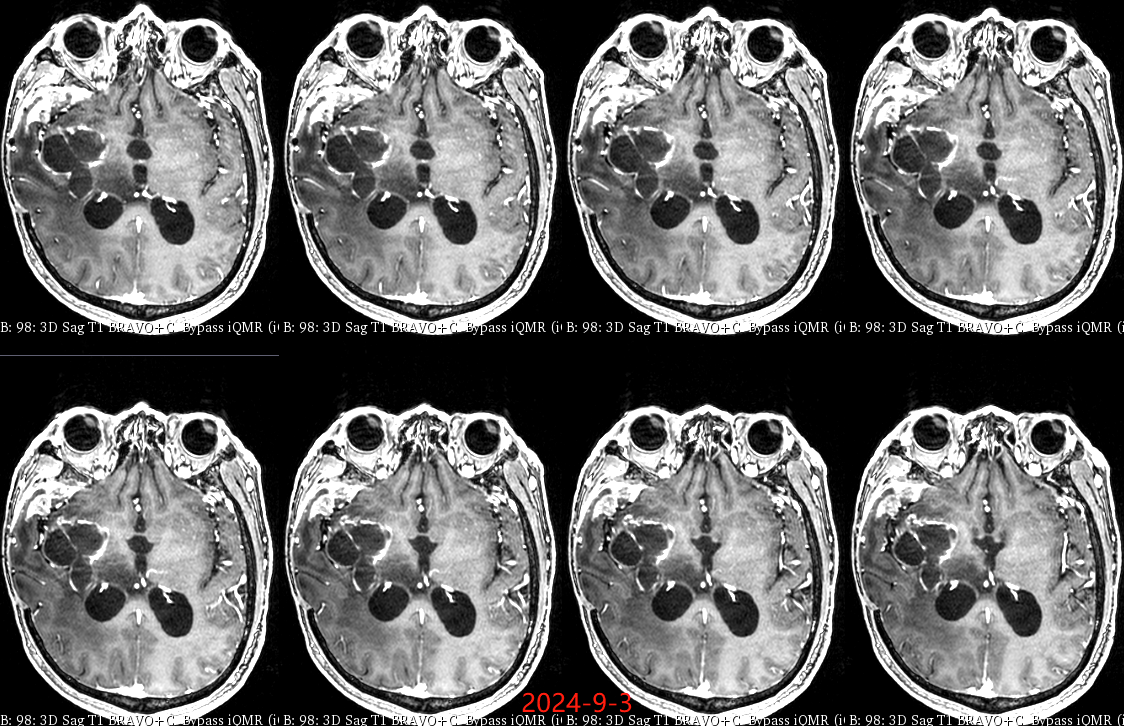

入院后于当地医院完善头颈部CTA检查未见明显血管发育异常,于2023-6-7行血肿钻孔引流术+脑室内颅内压监护探极置入术,引流一周后拔除引流管,期间未行尿激酶注射,患者反应情况逐渐好转,肌力未见明显改善。于出血后3周左右脑水肿基本消退后出院行康复治疗,治疗过程中患者肌力曾有所改善,左侧肢体肌力最好可达3级。术后3月左右患者一般状态逐渐变差,无发热,神志逐渐进展为昏睡状态,左侧肢体肌力1级,复查颅脑CT示水肿较前明显加重,颅脑MRI示右侧基底节区长T1长T2团块状病变,内有囊变,呈不均匀菜花样强化,考虑为高级别胶质瘤可能性大。遂行开颅病灶大部切除+去骨瓣减压术,术后病理提示高级别胶质瘤伴囊变,后续行同步放化疗STUPP方案,PTV:60Gy/30F/6周,替莫唑胺350mg化疗。患者右侧基底节区病灶相对稳定,2024-9-3复查颅脑MRI可见脑室内新发病灶。患者目前KPS 60分,神志清醒,精神差,反应迟钝,语言对答部分切题,右侧肢体自主活动,左侧肢体肌力2级。